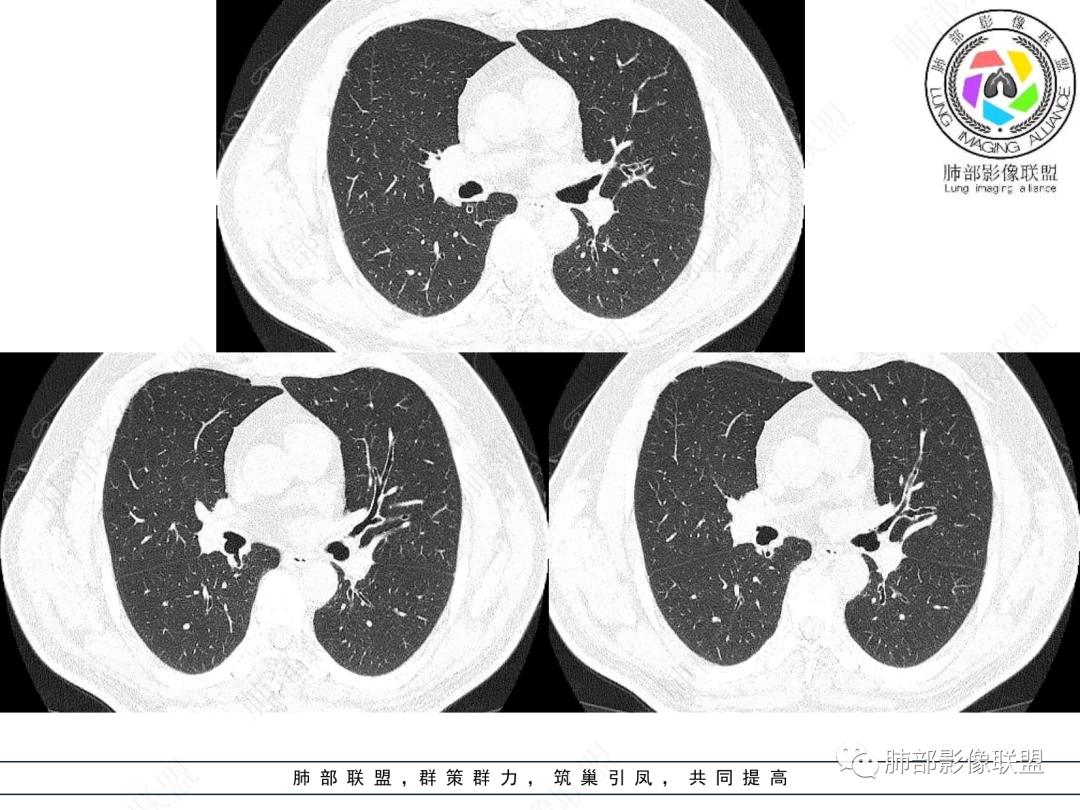

这个病例比较好,我们的观察点在哪?这是右上叶支气管病变,需要了解:腔内、壁、腔外、远端,腔内有软组织密度影,近端膨隆。

这是软骨

壁厚

红色:软骨连续性良好,壁外有软组织密度影,绿色:软骨不连续,破坏了,外面软组织密度影。

南边:提示软骨破坏,也就是病灶腔内朝壁外侵犯了——恶性。

远端支气管腔内不强化的是粘液栓,强化的是肿瘤。

影像上分析的观察点:腔内、壁、腔外、远端,然后就是远端肺组织、淋巴结、肺血管、胸膜、其他肺部,这个人就是阻塞性炎症为主。